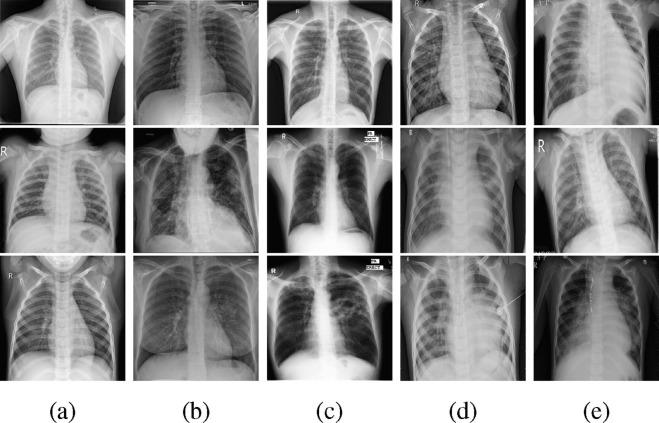

The early detection of infection is significant for the fight against the ongoing COVID-19 pandemic. Chest X-ray (CXR) imaging is an efficient screening technique via which lung infections can be detected. This paper aims to distinguish COVID-19 positive cases from the other four classes, including normal, tuberculosis (TB), bacterial pneumonia (BP), and viral pneumonia (VP), using CXR images. The existing COVID-19 classification researches have achieved some successes with deep learning techniques while sometimes lacking interpretability and generalization ability. Hence, we propose a two-stage classification method MANet to address these issues in computer-aided COVID-19 diagnosis. Particularly, a segmentation model predicts the masks for all CXR images to extract their lung regions at the first stage. A followed classification CNN at the second stage then classifies the segmented CXR images into five classes based only on the preserved lung regions. In this segment-based classification task, we propose the mask attention mechanism (MA) which uses the predicted masks at the first stage as spatial attention maps to adjust the features of the CNN at the second stage. The MA spatial attention maps for features calculate the percentage of masked pixels in their receptive fields, suppressing the feature values based on the overlapping rates between their receptive fields and the segmented lung regions. In evaluation, we segment out the lung regions of all CXR images through a UNet with ResNet backbone, and then perform classification on the segmented CXR images using four classic CNNs with or without MA, including ResNet34, ResNet50, VGG16, and Inceptionv3. The experimental results illustrate that the classification models with MA have higher classification accuracy, more stable training process, and better interpretability and generalization ability than those without MA. Among the evaluated classification models, ResNet50 with MA achieves the highest average test accuracy of 96.32 in three runs, and the highest one is 97.06 . Meanwhile, the attention heat maps visualized by Grad-CAM indicate that models with MA make more reliable predictions based on the pathological patterns in lung regions. This further presents the potential of MANet to provide clinicians with diagnosis assistance.